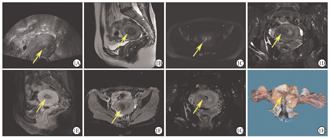

这11例UEC/DEC患者占本院同时期确诊为子宫内膜癌患者的1.8%(11/629),其一般临床、实验室、影像学及病理学检查结果如下。①临床资料:确诊时11例UEC/DEC患者的中位年龄为50岁(43~65岁),中位BMI为24.7 kg/m2;绝经后患者为8例,围绝经期为1例;有糖尿病者为2例;3代以内直系亲属有肿瘤史者为5例;手术方式为经腹者为5例,经腹腔镜者为6例;FIGO临床分期为早期(Ⅰ~Ⅱ期)者为6例,晚期(Ⅲ~Ⅳ期)者为5例。5例FIGO Ⅲ~Ⅳ者中,1例(No.3)伴腹主动脉旁淋巴结转移,2例(No.7、9)伴子宫外盆腔扩散,1例(No.2)同时伴卵巢和腹主动脉旁淋巴结转移,1例(No.8)伴远处髋臼转移。②主要临床表现:阴道不规则流血者为9例,下腹胀痛者为2例。③实验室检查结果:4例(No.2~3、9~10)患者血清肿瘤标志物糖类抗原(carbohydrate antigen,CA)125,人附睾蛋白(human epididymis protein,HE)4水平升高。④影像学检查结果:11例UEC/DEC患者的超声检查提示子宫内膜增厚或宫腔内有不均质回声团(图1A);MRI结果提示子宫内膜不规则增厚或宫腔内占位,呈等T1、稍长T2信号影,弥散加权序列上呈明显的高信号,表观弥散系数图呈低信号,增强扫描可见病灶强化(图1B,图1C,图1D,图1E,图1F,图1G)。1例(No.8)患者初诊时,MRI检查见右侧髋臼下缘不规则斑片状等T1、短T2信号影,DWI序列呈高信号,增强扫描见不均质强化,伴周围软组织肿胀(图2),经皮右侧髋臼穿刺病理学检查结果证实为DEC的未分化组分(undifferentiated components,UC)转移至髋臼。⑤术前组织病理学检查结果:10例(No.1、3~11)患者术前行子宫内膜活组织病理学检查,2例(No.7~8)确诊为DEC,2例(No.1、3)为子宫内膜腺癌,5例(No.4~6、10~11)为低分化子宫内膜癌,1例(No.9)为子宫内膜息肉,1例(No.2)未行子宫内膜活组织病理学检查。⑥术后病理学检查结果:3例(No.3~4、11)为UEC,8例(No.1~2、5~10)UC合并低级别子宫内膜样癌成分,3例(No.1、3、6)UC合并高级别子宫内膜样癌成分,其中1例(No.3)同时还合并高级别浆液性癌成分;肿瘤最大直径≤2 cm为2例(No.1~2),>2 cm为9例(No.3~11),其中1例DEC患者(No.8)子宫切除后剖视可见宫腔内病灶大小约为2.2 cm×1.8 cm×1.2 cm,累及子宫壁>1/2肌壁全层(图1H);肌层浸润深度<1/2为7例(No.2~5、7、10~11),≥1/2为4例(No.1、6、8~9);11例患者均无盆腔淋巴结转移;腹主动脉旁淋巴结转移为2例(No.2~3),淋巴脉管间隙浸润为5例(No.4、6、8~10)。

注:DEC为去分化子宫内膜癌